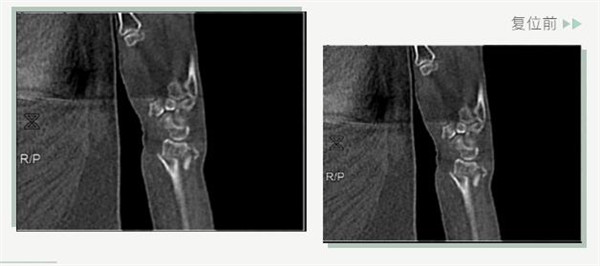

復(fù)位前

25日當(dāng)天,莊阿婆來到危立軍副院長門診,經(jīng)拍片顯示,莊阿婆左橈骨遠(yuǎn)端粉碎性骨折,左髂骨至髖臼后緣及恥骨下支骨折??紤]到莊阿婆年紀(jì)較大,基礎(chǔ)病較多,難以經(jīng)受手術(shù)創(chuàng)傷,傳統(tǒng)手法復(fù)位更為合適。推、拽、按、捺……經(jīng)過危立軍副院長一番手法復(fù)位后,再次拍片顯示莊阿婆橈骨遠(yuǎn)端骨折端復(fù)位位置良好,莊阿婆及其家人感到非常滿意。

復(fù)位后